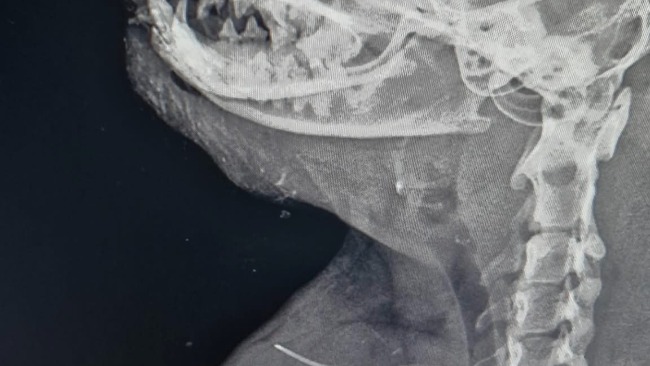

Zdiagnozowano złamanie kości przedramienia prawego i spojenia żuchwy. Usg jamy brzusznej nie wykazało odchyleń od normy. Kot został zabezpieczony przeciwbólowo i czeka na zabieg osteosyntezy.